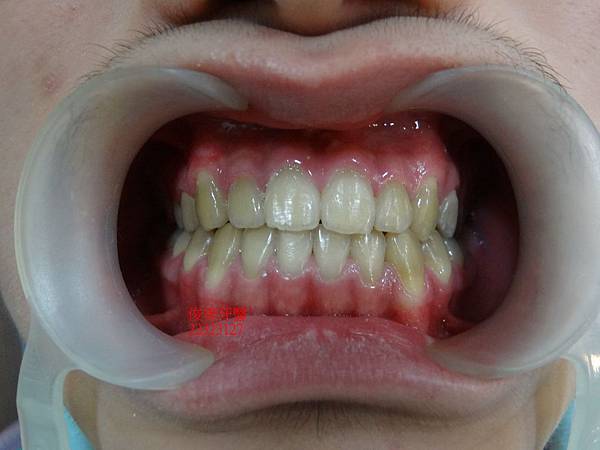

經拍照記錄原始狀況..

患者戽斗的狀況在小孩子來說, 算是比較中、重度的

但因孩子骨架尚在發育, 有成長空間, 此時將牙齒調整為正常咬合,

才有辦法帶動骨頭生長....